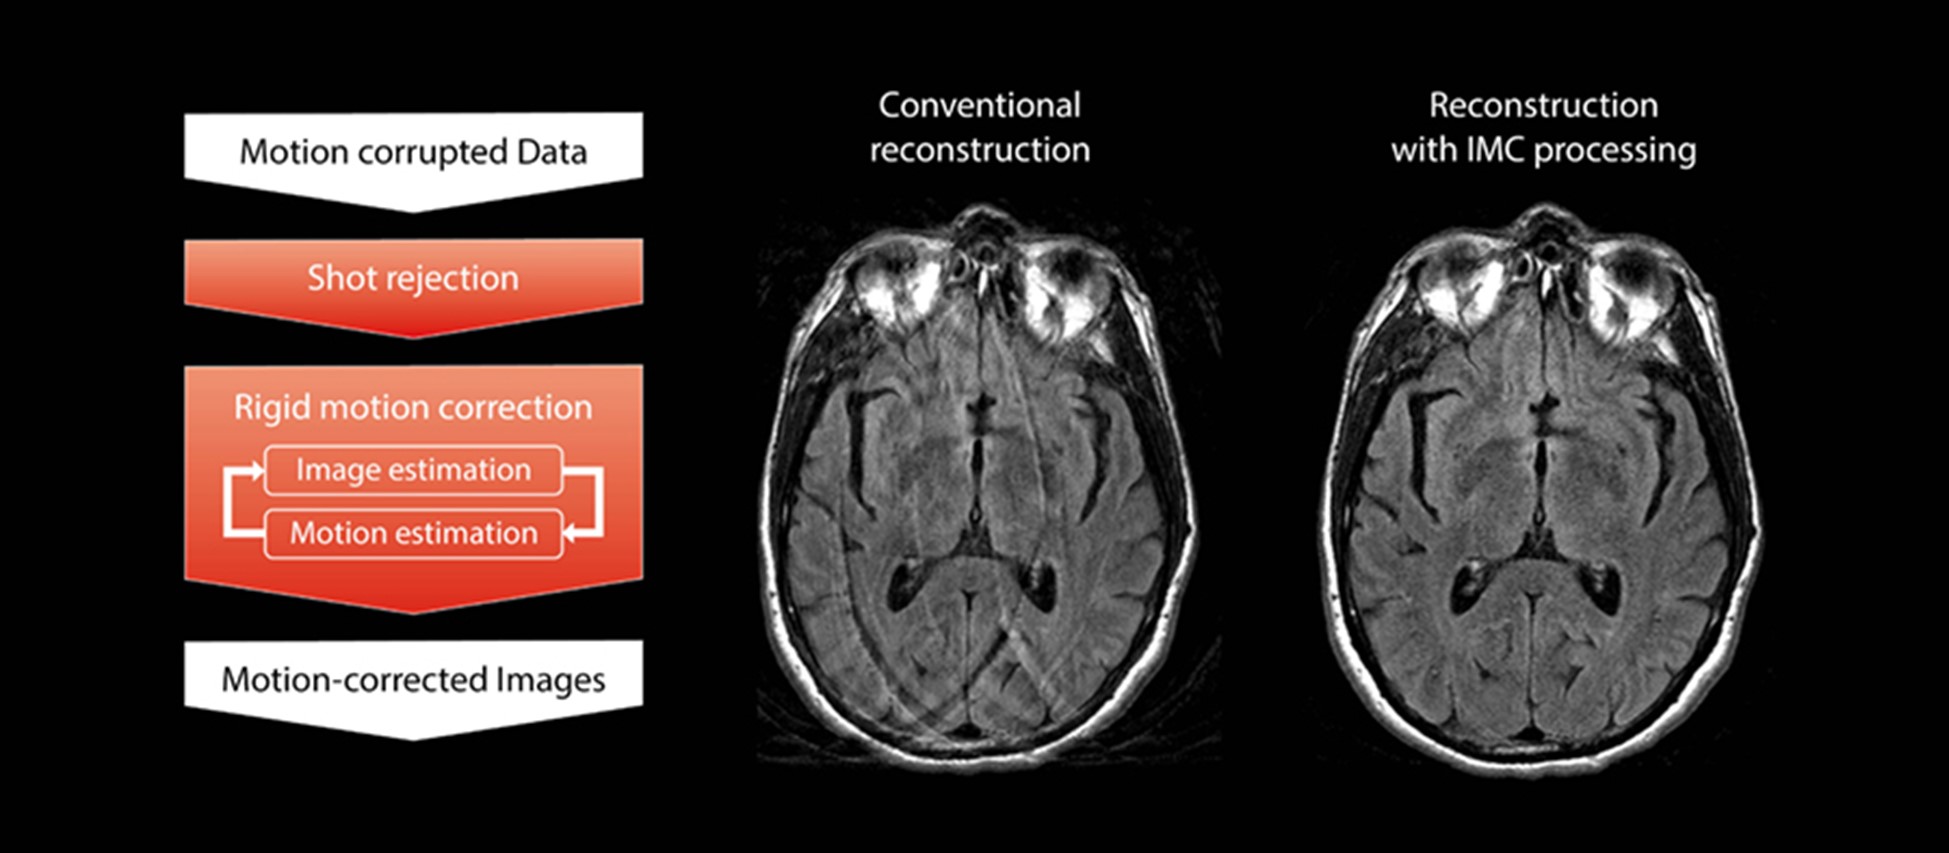

Корекцію IMC можна застосувати до руху твердого тіла, наприклад голови. Рух твердого тіла спрощується, для того, щоб оцінити та виправити величину переміщення та обертання. Процес показано на рис. 1. IMC завжди використовує свого роду паралельну реконструкцію зображень, щоб отримати дані FSE із неповною вибіркою, і це сприяє скороченню часу сканування, порівняно зі звичайним клінічним скануванням.

Як показано на рис. 1, існує два процеси корекції твердого тіла. Спочатку процес відбору даних використовує алгоритми виявлення руху, щоб усунути дані з сильним рухом. Після цього процес корекції руху твердого тіла використовує дані, що залишилися, і виконує оцінку як кількості руху (оцінка руху), так і зображень без руху (оцінка зображення) шляхом винайденя невідомих параметрів.

Рис. 1: Блок-схема процесу реконструкції Ітеративної Корекції Руху для руху твердого тіла (ліворуч) і порівняння зображень із/без IMC (праворуч)

Процес оцінки зображення використовує метод Conjugate Gradient SENSE (SENSitivity Encoding) для оцінки очікуваного остаточного реконструйованого зображення на основі зібраних даних із неповною вибіркою. Потім процес оцінки руху моделює дані k-простору з певною кількістю руху тіла шляхом додавання параметрів руху (величини поступального та обертального руху). Змодельовані та фактично зібрані дані порівнюються в області зображення, щоб знайти значення для невідомих параметрів з мінімальною помилкою.

Оскільки помилка не може бути мінімізована цією обробкою лише за один раз, оцінка зображення та оцінка руху повторюються по черзі та ітеративно. Наприкінці, отримується реконструйоване зображення, зі зменшеним впливом руху.